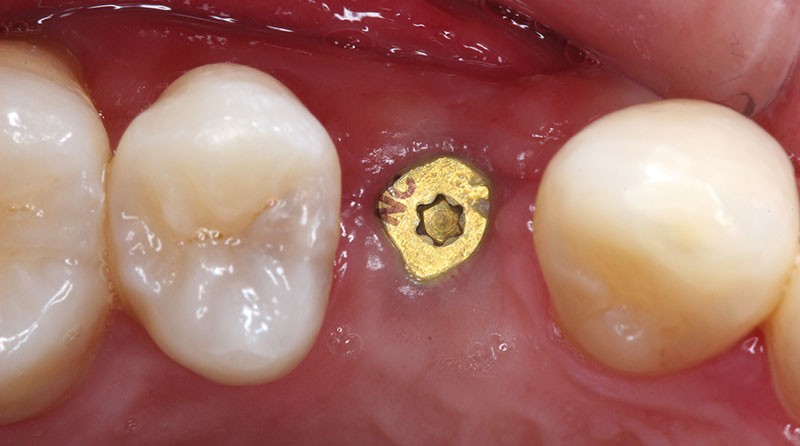

Examen clinique

Un jeune patient consulte pour combler un édentement unitaire en 14. Un implant dentaire (Bone Level NC®, Straumann) est mis en place en respectant un projet prothétique ayant pour finalité une prothèse implantaire transvissée. Après trois mois, l’ostéointégration est validée cliniquement et radiologiquement, la réhabilitation prothétique peut alors débuter (fig. 1).